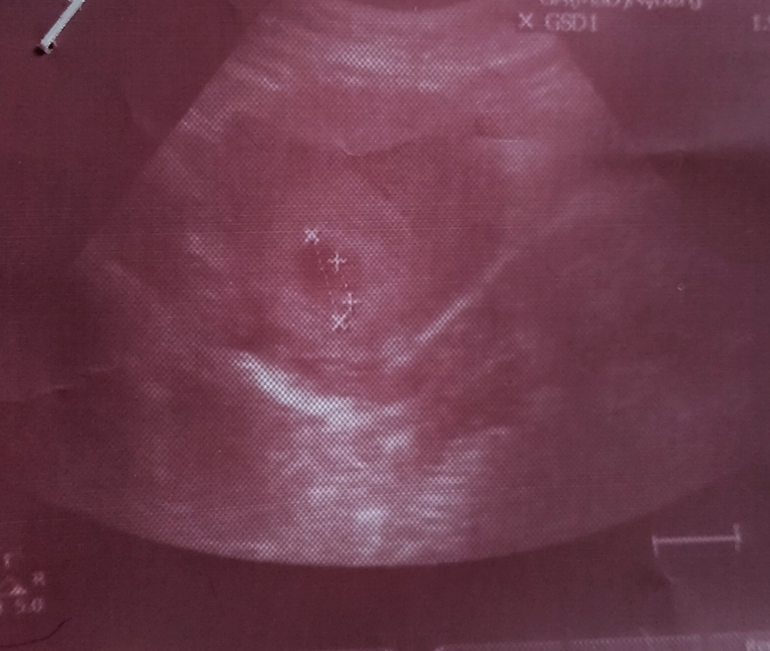

УЗИ абдоминальное, через живот. Срок 7+3